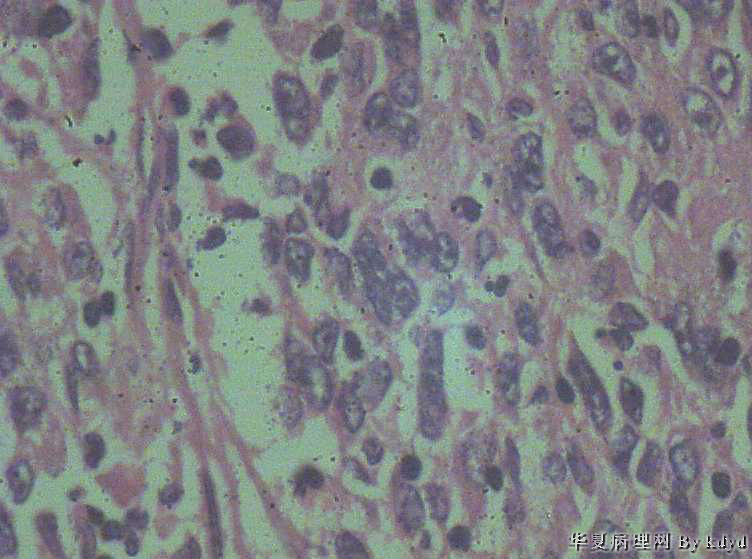

B3997左乳肿瘤--浸润性导管癌?

37岁,女。左侧乳腺肿块发现5个多月,伴隐痛。

手术见:肿块与周围组织分界不清,无明显包膜。

大体:不整形组织大小约3.5*35*2CM,未见明显包膜。质较软,切面浅黄色,一侧见一小囊腔直径约0.8CM囊壁较粗糙。

• 左乳肿瘤--浸润性导管癌?图2

图2

标签:乳腺浸润性导管癌 原位癌

浸润性乳腺导管癌?

IDC

乳腺浸润性导管癌

囊壁内大量炎细胞浸润,囊壁被覆细胞有明显异型,可见核分裂,考虑癌,不知有无陷阱

考虑癌,但切片质量有点欠缺,发癌有点底气不足!

浸润性导管癌